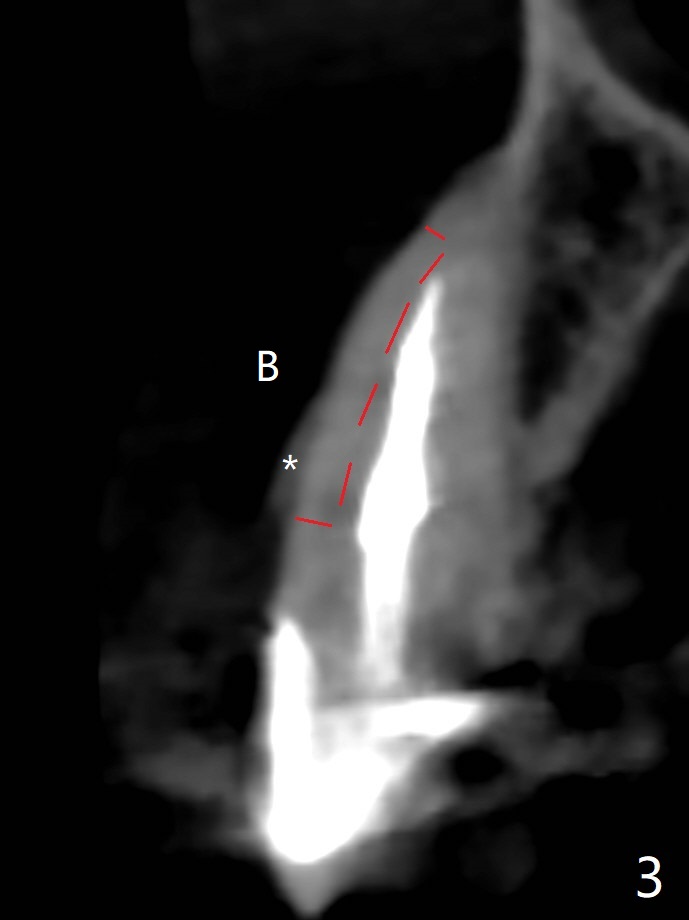

防止拔牙后颊侧骨板萎缩最有效方法是保留部分牙根,例如颊侧(外形象盾牌,简称盾,socket shield (S)),但是制备特别麻烦,尤其是上尖牙。60岁女右上3颊侧骨板隆起(图一至三:*),但是相当狭窄(上下方向),预计强行拔除,势必损失颊侧骨板,造成颊侧塌陷,准备保留盾,如图三红虚线,图六(术后3D长轴断面(十字架:植体))S代表。其实术中试图将整个牙根一起拔除,但是仿佛不行,只好静下心来分根,制备盾,不过困难重重,尤其是除去根尖(防止残余感染),最长外科裂钻似乎达不到根尖,取出后者,颊侧根尖骨板穿孔(图七:箭头)。然后腭侧钻洞(图四),当最后一个钻头保持原位时,在颊侧根尖穿孔处植入粘性骨粉(从牙槽窝口进入,原本粘性骨粉为了修复大面积颊侧缺损用(万一需要强行拔除)),然后才把一段式植体植入(图五),在其余空间填入骨粉,稍微制备基台,制作临时牙冠,最后在牙槽窝开口塞入PRF膜,衬里牙冠,不暂时取出牙冠,衬里相当于临时粘固剂。术后一个月牙根片段和临时牙冠维持良好的牙龈外形(图八,九);术后两个月病人嫌尖牙龈端太尖太长,临时牙冠龈端调整(图十,十一),但愿一个月后龈缘合乎病人期望。